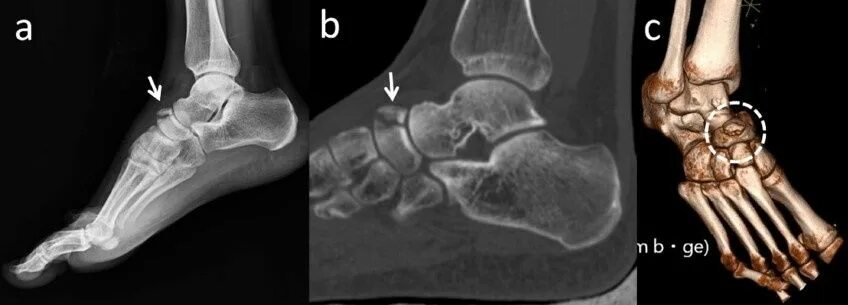

Пяточная остеотомия